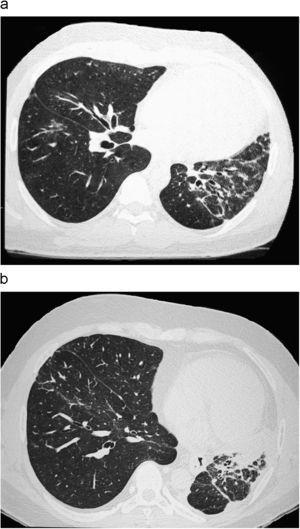

Paciente varón de 35 años de edad, que 5 años atrás había ingresado para estudio de hemiatrofia corporal y trastorno cutáneo izquierdo. En ese momento sólo refería debilidad muscular del lado izquierdo y se encontraba asintomático desde el punto de vista respiratorio. Durante la exploración física se observó leve atrofia de la musculatura de la hemicara y hemilengua izquierdas, así como pérdida del vello en el hemitórax izquierdo y telangiectasias, lesión lineal frontal izquierda que parecía afectar la piel y el tejido subcutáneo, además de importante atrofia muscular de predominio en la zona distal inferior izquierda. En las pruebas analíticas efectuadas sólo destacaron unos títulos de anticuerpos antinucleares de 1/320, C3 de 90mg/dl y C4 de 15mg/dl; los anticuerpos contra antígenos nucleares extraíbles, anti-Ro, anti-La, anti-Sm, ScL-70, anti-Jo1, anti-PM1, citoplásmicos antineutrófilos, antimitocondriales y anticentrómero fueron negativos, y la función renal y hepática, normal. El resto de pruebas complementarias efectuadas (radiografía de tórax y pruebas de función respiratoria) mostraron normalidad. Con todos estos datos, se llegó al diagnóstico de esclerosis localizada tipo morfea en coup de sabre. Un año y medio más tarde, se envió al paciente al Servicio de Neumología por disnea de esfuerzo y anormalidades en la radiografía de tórax, consistentes en pérdida de volumen en el hemitórax izquierdo con afectación intersticial homolateral reticular de tractos gruesos. Se le efectuó una tomografía computarizada de alta resolución, donde se confirmó la existencia de un infiltrado intersticial en el hemitórax izquierdo (figura 1a); el resto del parénquima era normal. Se le realizaron pruebas de función respiratoria, que demostraron una restricción leve-moderada, con una capacidad vital forzada (FVC) de 3.030ml (68%), volumen espiratorio forzado en el primer segundo (FEV1) de 2.550ml (67%), FEV1/FVC del 83% y capacidad pulmonar total de 4.190ml (66%). En la prueba de la marcha de 6min recorrió una distancia de 542m y alcanzó una saturación de oxígeno mínima del 95%. Al cabo de un año, el paciente manifestó mayor grado de disnea. La radiografía de tórax evidenció mayor pérdida de volumen en el hemitórax izquierdo, y la tomografía computarizada de alta resolución, una progresión importante del patrón intersticial (figura 1b), que se corroboró en las pruebas de función respiratoria, donde la FVC fue de 2.430ml (55%), el FEV1 de 1.800ml (48%), FEV1/FVC del 74% y capacidad pulmonar total de 3.010ml (48%). En la prueba de la marcha de 6min recorrió 500m y alcanzó una saturación de oxígeno mínima del 87%. Tras haber comprobado la progresión de la enfermedad pulmonar se decidió aumentar la dosis de esteroides y comenzar con azatioprina, tras lo cual se observó la estabilización de la afectación pulmonar.

Figura 1. a: leve afectación intersticial en el hemitórax izquierdo. b: progresión de la enfermedad al cabo de un año.